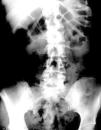

Síndrome constitucional, fiebre y dolor en flanco izquierdo en mujer de 41 años

41-year-old female with constitutional syndrome,fever,and pain in left flank